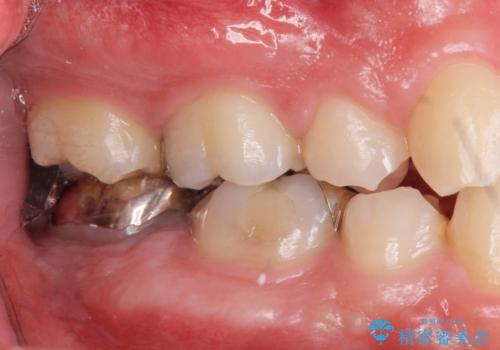

手前の銀の詰め物のところは除去して拡大鏡下で虫歯を取り除き、ジルコニアクラウンで治療を行いました。

抜歯したところは抜歯後骨の治癒を待ち、CTを撮影しインプラント治療ができる事(骨の厚みなど)確認し治療を行いました。

白くて綺麗な被せ物が入りました。